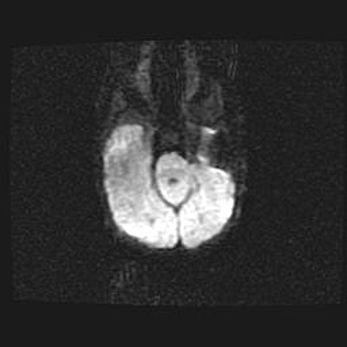

Церебральная ишемия II.

Возраст: 5 дней

Вес: 3400 г

Пол: женский

Окружность головы: 35 см

Срок гестации: 39 недель

Церебральная ишемия – это заболевание, характеризующееся недостаточностью (гипоксией) либо полным прекращением (аноксией) снабжения мозга кислородом по причине закупорки одного или нескольких сосудов. Это приводит к  что метаболическим расстройствам различной степени тяжести в тканях головного мозга, развитию коагуляционных некрозов и гибели нейронов.